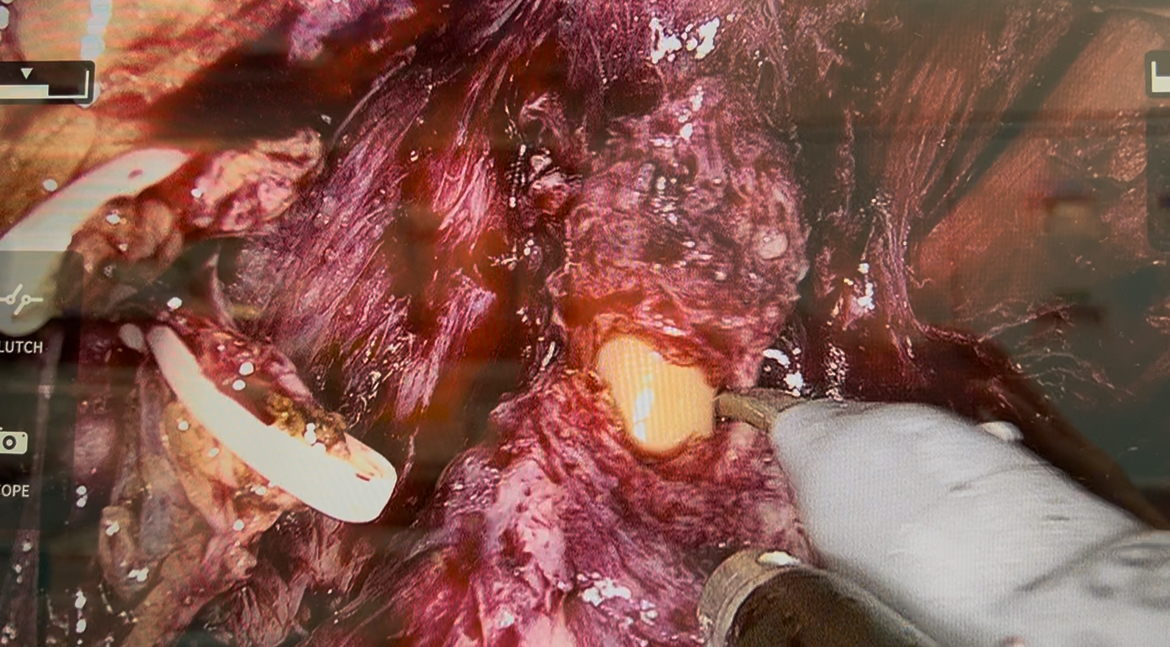

膀胱頚部と前立腺底部の境界部分をすでに膀胱内に留置されているバルーンカテーテルのバルーンの位置を頼りに膀胱前面を切開し、膀胱内に到達。その後膀胱後面を離断して精嚢腺に到達。左右の精管膨大部を離断して、両側の精嚢腺をデノンヴィエ筋膜から剥離し、デノンヴィエ筋膜を切開して直腸前面まで達したところで前立腺を前方に起こしながら左側の神経血管束をへモロックでクリップしながら切断し、対側の右側の神経血管束は温存のため、切断せずに前立腺と右側神経血管束の剥離面を分けていきながら、前立腺尖部に到達。その後、恥骨前立腺靭帯を切除して行きDVC前面に到達。深陰茎背静脈(DVC)という太い静脈叢を処理する際に気腹圧を8mmHgから12mmHgに上昇させた結果、無結紮で切断してもほぼほぼ出血せず尿道前面まで到達。我々の開腹手術しか行っていない世代の人間は、ここのDVC(深陰茎背部静脈)を結紮してからの切断(”バンチングテクニック”といういかにも高度な技術かのように命名されていた・・・)が一番出血する部位として恐れられておりましたので、いくら気腹しているといってもなんか現実を受け入れられないジレンマに陥ってしまいました。その後、V-Locという返しの付いた特殊な吸収糸を用いて連続縫合し、気腹圧を下げても出血無き事を確認。なんか簡単に処理しちゃってるよなー、って我々の苦労は何だったのか?いや、これが文明の理、医学の進歩(というより医用工学の発展が目覚ましい訳で、医学自体が進んだ、医者の技術が向上した、という風には一概には言えない様な・・)なんだとまざまざと見せつけられました。その後、尿道前面を切開し、バルーンカテーテルを同定して引き抜き、尿道後面を切断して無事前立腺は摘除されました。

DVC(深陰茎背静脈)を気腹圧を上げて無結紮で切断しているところ。